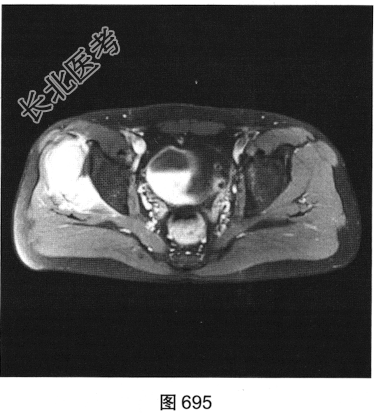

- [材料题] 患者为中年男性,发现右髋部外上方包块伴疼痛3周,以胀痛为主,包块大小为5cm×4cm,质硬,无发热、流脓流血,右下肢关节的感觉、活动、血运正常,自服止痛药治疗,疼痛稍有所缓解。查体:皮肤黏膜色泽正常,浅表淋巴结未触及,局部皮温稍高,皮肤无溃疡。

- 多项选择题2.[提示]患者行MRI平扫及增强扫描,见图692~图697。患者MRI平扫及增强扫描图像有哪些阳性表现( )

A、肿块边界不清,信号不均匀

B、肿块周围水肿明显

C、增强扫描肿块呈均匀强化

D、肿块边界清楚,信号均匀

E、增强扫描肿块及周围软组织呈明显不均匀强化

F、与邻近肌肉相比,T1WI呈等信号;T2压脂序列呈明显高信号